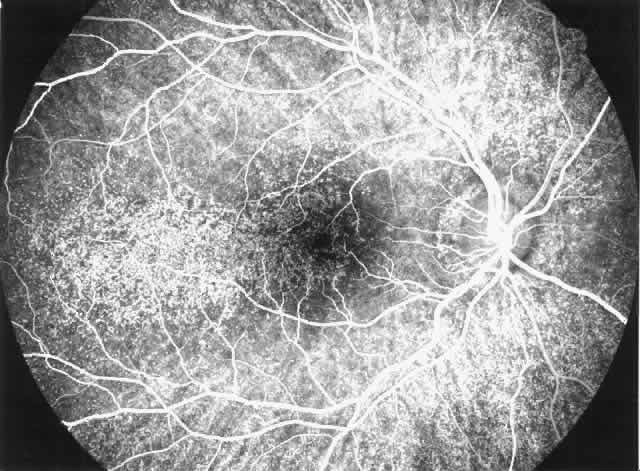

disease, which is probably independent of treatment and age of the patient.77–79  Fig. 6. Specific fundus lesions of membranoproliferative glomerulonephritis type

II in a 12-year-old child with renal disease since the age of 3 years. The

fluorescein angiogram shows numerous small lesions similar to hard

drusen. (Leys A, Vanrenterghem Y, Van Damme B et al: Fundus changes in membranoproliferative

glomerulonephritis type II: A fluorescein angiographic study

of 23 patients. Graefes Arch Clin Exp Ophthalmol 229:406, 1991) Fig. 6. Specific fundus lesions of membranoproliferative glomerulonephritis type

II in a 12-year-old child with renal disease since the age of 3 years. The

fluorescein angiogram shows numerous small lesions similar to hard

drusen. (Leys A, Vanrenterghem Y, Van Damme B et al: Fundus changes in membranoproliferative

glomerulonephritis type II: A fluorescein angiographic study

of 23 patients. Graefes Arch Clin Exp Ophthalmol 229:406, 1991)